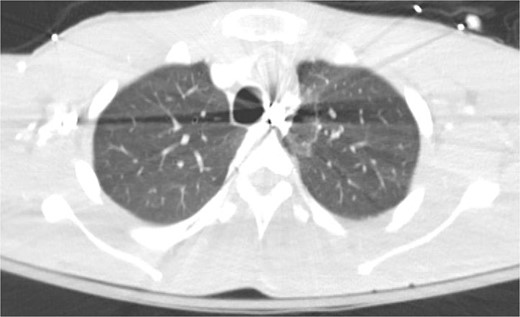

A 21-year-old male with a GSW to the left scapula presented to our Level 1 trauma center. He was stable but had flaccid paralysis and no rectal tone. A chest X-ray showed a bullet in the upper mediastinum (Fig. 1), prompting a computed tomography (CT) angiogram. The CT revealed a C6 cervical spine fracture, epidural hematoma, pneumomediastinum, and the bullet in the mediastinum at approximately the level of T3, but no hemorrhage (Fig. 2). Immediate upper endoscopy and bronchoscopy under general anesthesia were normal. He was extubated and monitored in the trauma ICU.